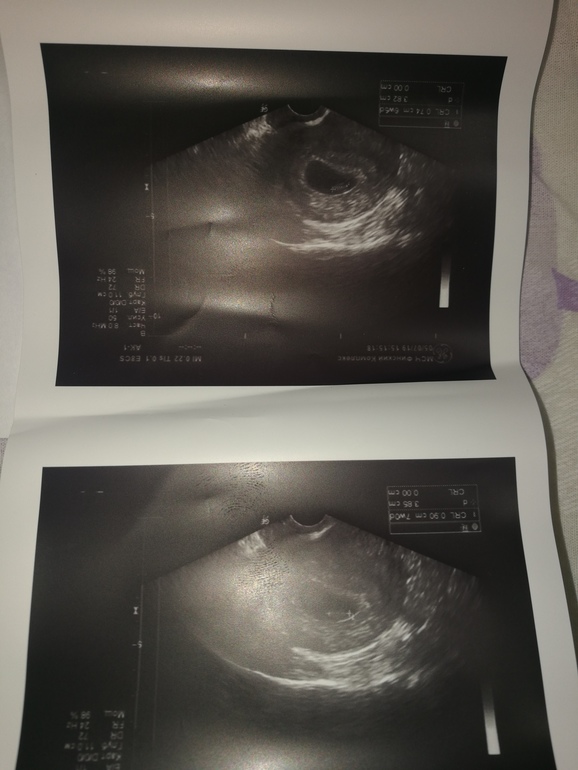

Сходила на УЗИ развеять свои страхи. 8 неделя Б

Поздравляю. На девочку похоже по методу рамзи). Хорошей, легкой беременности!

У меня такое же фото. Гинеколог как увидела ... сразу сказала девочка. По методу рамзи 97%. Но есть еще 3%. Желаю исполнения всех мечт)

Добрый день, сегодня подтвердили девочку